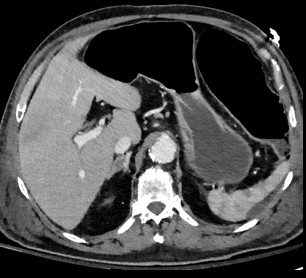

Choc

• Choc